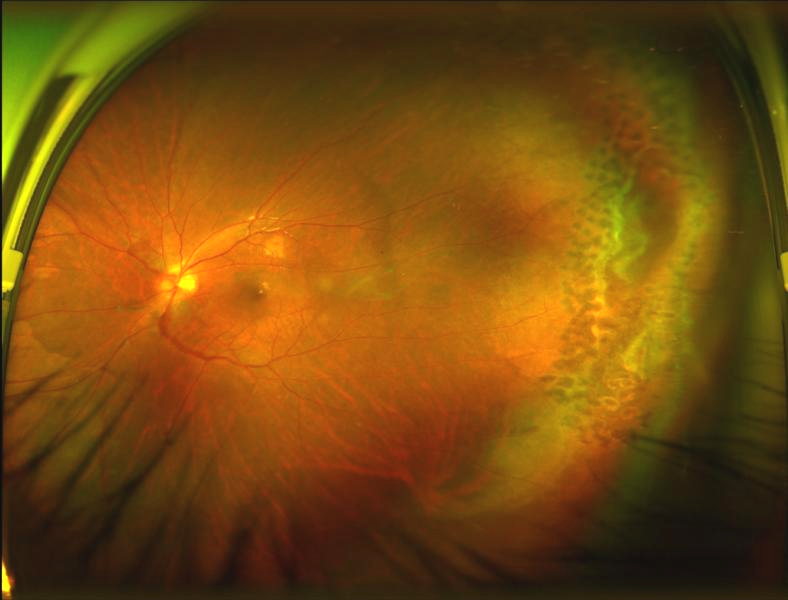

經(jīng)過檢查,陳燕副主任發(fā)現(xiàn)小曾的傷眼已發(fā)生視網(wǎng)膜脫離,需要盡早手術(shù),否則有失明的風(fēng)險。

小曾術(shù)前眼底照相